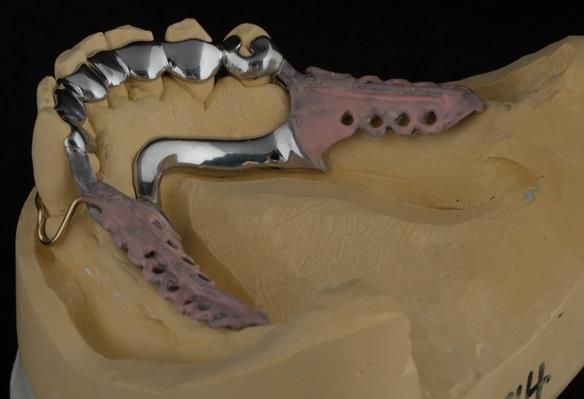

- Definitive dentures (Mk 2) – complete upper metal reinforced and lower cobalt chromium based partial of hygienic Scandinavian design to be made 9 - 12 months after extractions of all upper teeth and LR5 and LL4

The clinical situation and treatment process is shown in detail below with photographs.

The patient has been successfully rehabilitated and is now having periodontal maintenance from Syed Abad, Specialist in Periodontics at the practice. His quality of life has improved considerably. The clinical prosthodontics was provided by me and the technical work by Rowan.